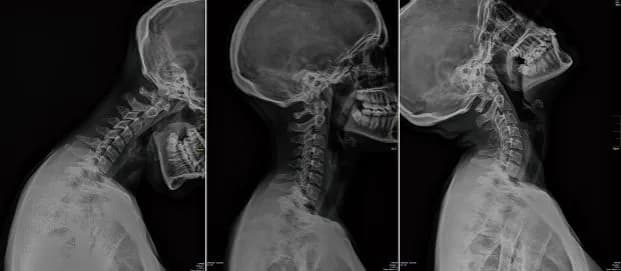

Skręcenie kręgosłupa szyjnego ile zwolnienia? Dowiedz się, jak długo trwa zwolnienie lekarskie i jakie czynniki wpływają na jego długość.